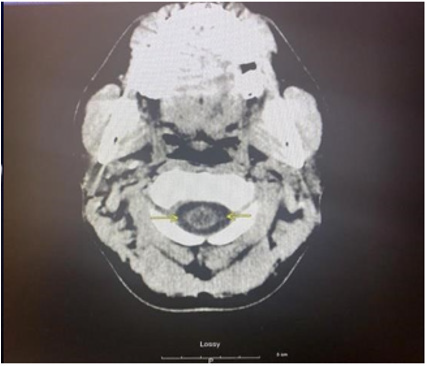

As part of the workup for the patient, a CBC with differential, chemistry panel, CT of the cervical area and ECG were ordered. The CBC test revealed leukocytosis at 13 cells/uL with 80.6% neutrophil and 10.3% lymphocyte relative count. Furthermore, the patient was found to have thrombocytosis at 555x103 cells/uL. The chemistry panel also detected some abnormalities regarding the patient. Calcium and total bilirubin level were elevated at 11.1mg/ dL and 1.7mg/dL respectively. Looking further into the bilirubin count, the patient was found to have an elevated direct bilirubin level of 0.4mg/dL and an elevated indirect bilirubin count of 1.3mg/ dL. Lastly, the patient had a D-Dimer level less than 215ng/mL and a low Creatine Phosphokinase level at 57 U/L. To investigate potential neurological etiologies of the patient’s condition, a noncontrast CT scan was done in three areas of the patient: the brain, face, and cervical spine. The CT scans of the head and cervical spine are indicated by images A and B respectively. Imaging of the brain revealed dilation of lateral ventricles, 3rd ventricle and the cerebral aqueduct. The 4th ventricle, however, was normal in size. The presence of this abnormality definitively indicates the presence of obstructive hydrocephalus. Furthermore, hypoattenuation was detected around the ventricles in the cerebral and cerebellar area. The CT scan found no extra-axial fluid accumulation or depressed skull fractures. Next, facial area imaging found no signs of fractures, temporomandibular joint dislocation, orbital abnormalities, or sinus obstructions. Lastly, while CT imaging of the cervical spine indicated misalignment of the C5 and C6 vertebral bodies, this was likely attributed to motion artifact. In addition, other significant findings include disc narrowing between C7 and T1 and a hypodense appearance of the cervical spinal cord. Other than the abnormal findings, imaging indicated proper cervical spine alignment with no fractures, or prevertebral edema.

In terms of prognosis for the patient, studies show that significant deleterious effects may occur in the long run if hydrocephalus is not treated promptly [5]. Therefore, it is imperative to find the underlying etiology that led to the occurrence of hydrocephalus within the patient. The most probable cause of noncommunicating hydrocephalus within the patient’s age demographic is a ventricular lesion [5]. Nevertheless, no specific tumors were identified on the CT or the MRI making the presence of an obstructive neoplasm unlikely. A potential differential diagnosis can be made for idiopathic cerebral aqueduct stenosis based on the CT imaging indicating dilation of the first three ventricles but not the fourth cerebral ventricle.

Other differentials can also be explored based on the initial imaging of the patient. For instance, the early radiologic finding of ependymal lining enhancement, extensive to the level of T9, is highly suspect of ventriculitis. However, multiple pathologies could explain this event. Although a shunt may be able to explain this finding, leakage of the CSF, as well as meningitis are other possible causes [3]. While the discovery preceded surgical intervention in this patient, ventriculitis may also occur in response to invasive surgical procedures which manage hydrocephalus [4]. Additional analysis of the CT performed on the head, and cervical spine demonstrates changes in neuroanatomy, such as dilated ventricles, resulting from high intracranial pressure. These findings can additionally point towards potential causes of the hydrocephalus. For example, in noncommunicating hydrocephalus caused by spinal cord edema, swelling that extends to at least two vertebral segments above an injured portion is a diagnostic finding [9]. Furthermore, the absence of extra-axial fluid collection is used to rule out potential hydrocephalus ex-vacuo [10].